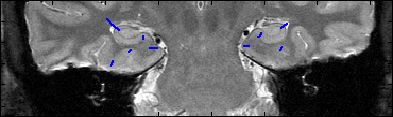

This is an example of one subjects demarcation. The A/P slice is slice

3.

3